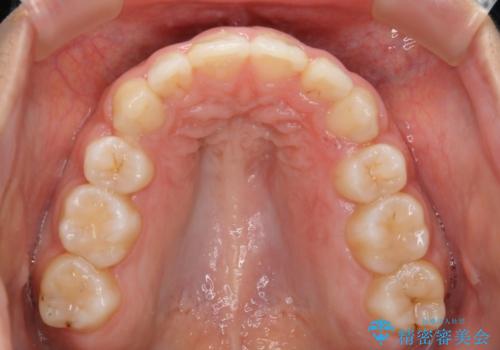

- 2年6ヶ月

- 30回以上

しっかりと口元・顔貌まで変化を起こせるように上下左右の第一小臼歯を抜歯し、ワイヤー装置にて矯正を開始することとなりました。